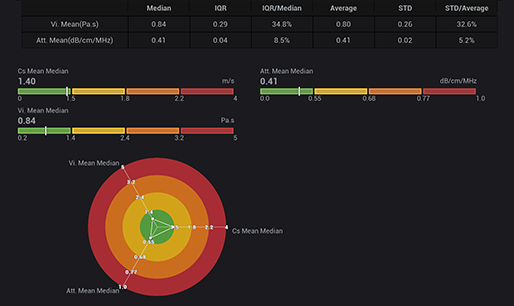

STVi consente la valutazione quantitativa della viscosit├Ā dei tessuti e fornisce immagini multiparametriche in tempo reale, offrendo un approccio pi├╣ completo alla diagnosi per immagini e all'analisi quantitativa di malattie epatiche croniche, lesioni mammarie e altre condizioni.

Valutazione della malattia epatica cronica

Strumenti di quantificazione multipli